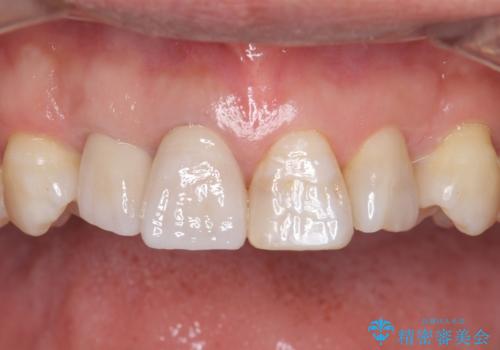

仕上がりに限界はありましたが、比較的短期間で歯並びが整いセラミック治療を行うことができ、患者様に「治療して良かった」とご満足頂けました。

左上1の歯の表面にもともと凹凸とグラデーションがあり、気になるようならセラミックでかぶせるのも一つだと提案しましたがご希望されなかったため、その表面性状を再現して右上1のセラミッククラウンを作製しています。

右上21:ジルコニアクラウン スペシャル